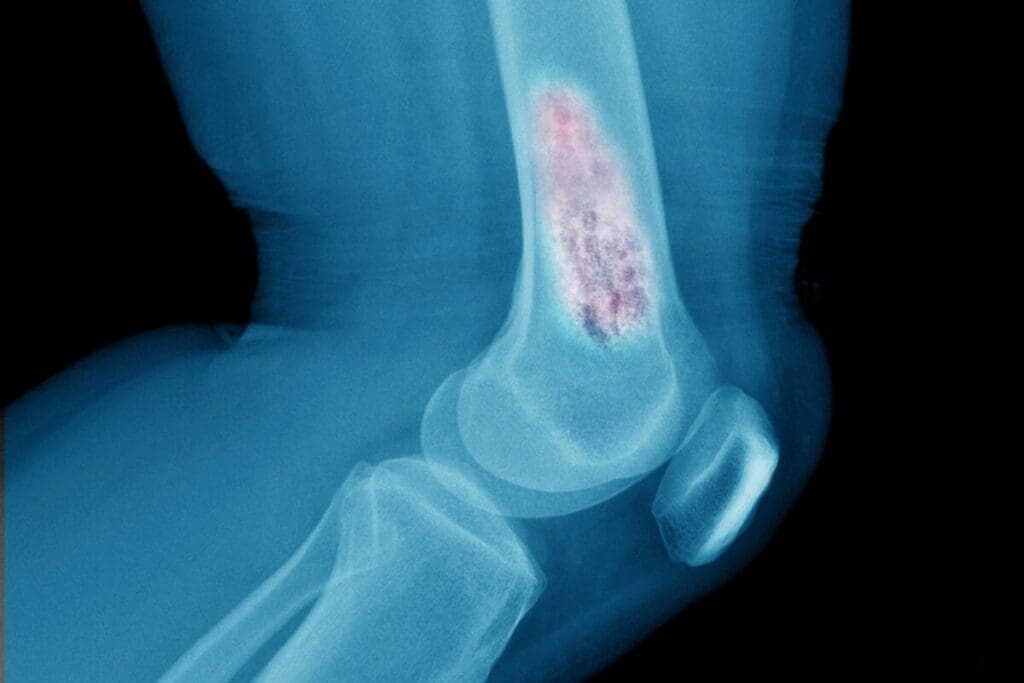

Benign tumors are not cancer and don’t spread. But, they can grow and harm nearby bone and tissue. Osteochondroma is a common benign tumor in kids. Malignant tumors, likeosteosarcoma, are cancerous and can spread, posing a bigger risk.

Where bone tumors occur in kids can vary. For example, osteosarcoma often hits the long bones in the legs. Other types might be found in the pelvis or spine.

Osteochondroma is the most common benign bone tumour in kids. It shows up in the metaphyses of long bones. This condition grows cartilage-capped bony projections on bones.

Osteochondroma, also known as an exostosis, is a benign tumour. It usually grows near the ends of long bones, like the femur, tibia, and humerus. It has a cartilage cap on a bony stalk, connected to the bone underneath.

Diagnostic Methods and Imaging

- Imaging Studies: X-rays, CT scans, MRI scans, and bone scans help find the tumor’s location, size, and how far it has spread.